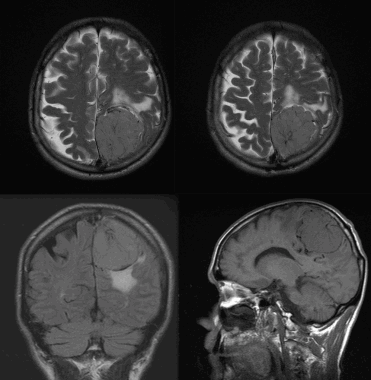

Менингиома теменной области. МР-изображения, полученные с использованием следующих последовательностей: аксиальное Т2-взвешенное, аксиальное Т2-взвешенное, корональное FLAIR -изображение и сагиттальное Т1-изображение. Крупная левосторонняя менингиома выглядит в виде экстрааксиального образования с паттерном «колеса со спицами» и отеком окружающих тканей.